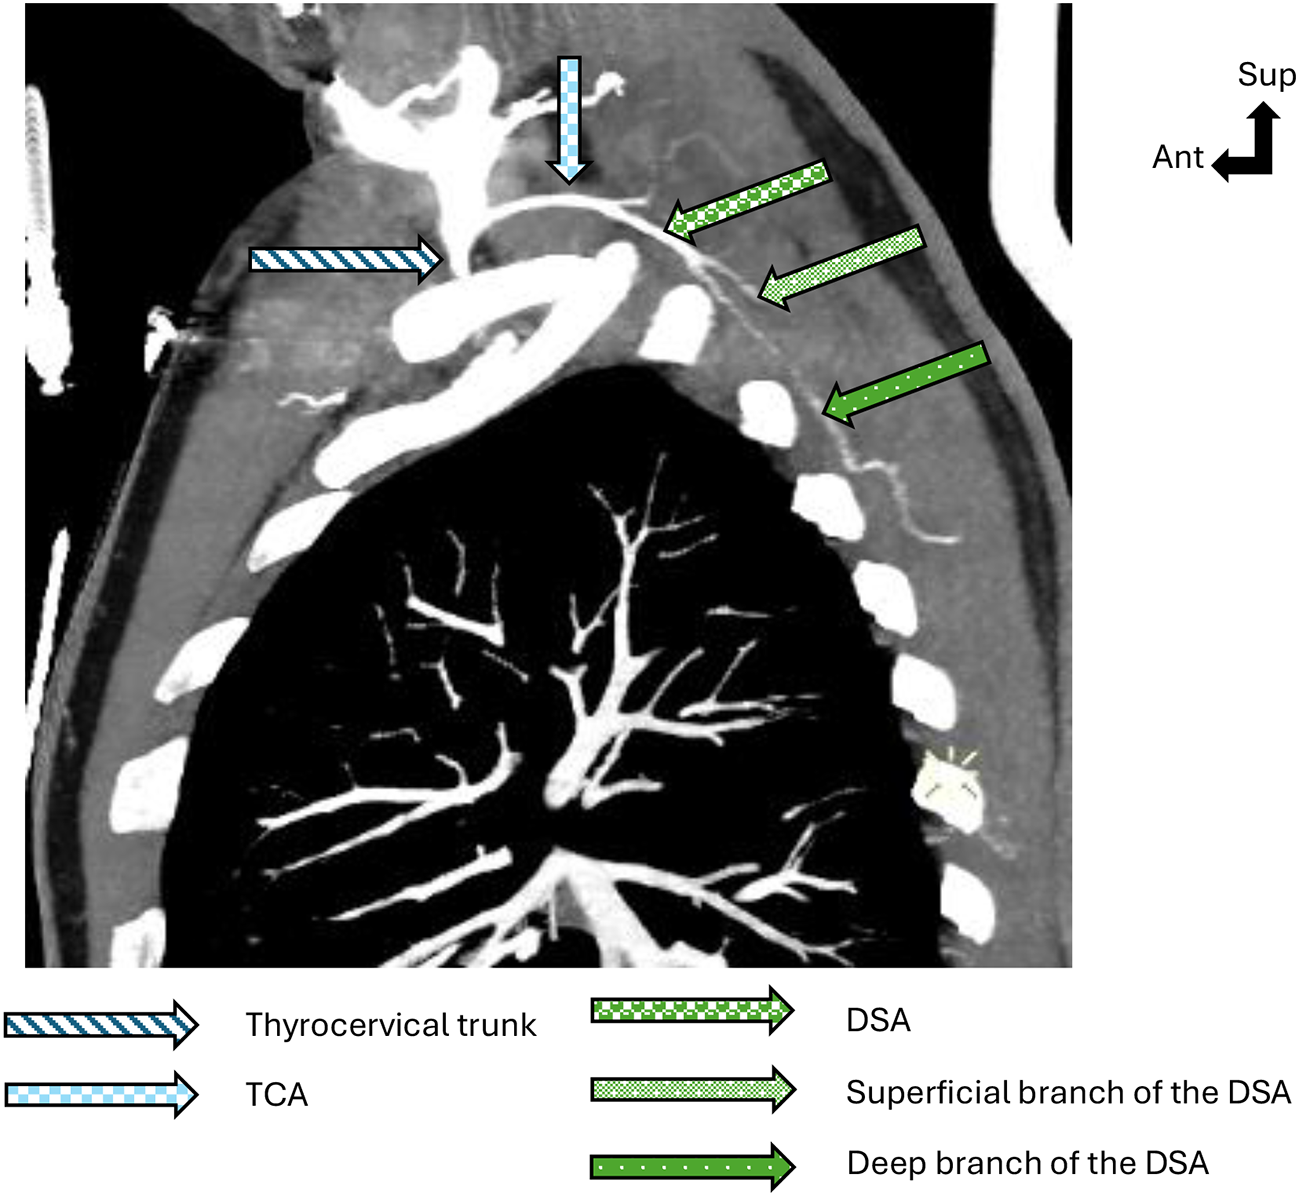

Anatomical study of the vascularization of the pedicled osteo-myo-cutaneous scapulo-dorsal flap

The main objective of this study was to conduct a radioanatomical study of the osteo-myo-cutaneous scapulo-dorsal pedicled...